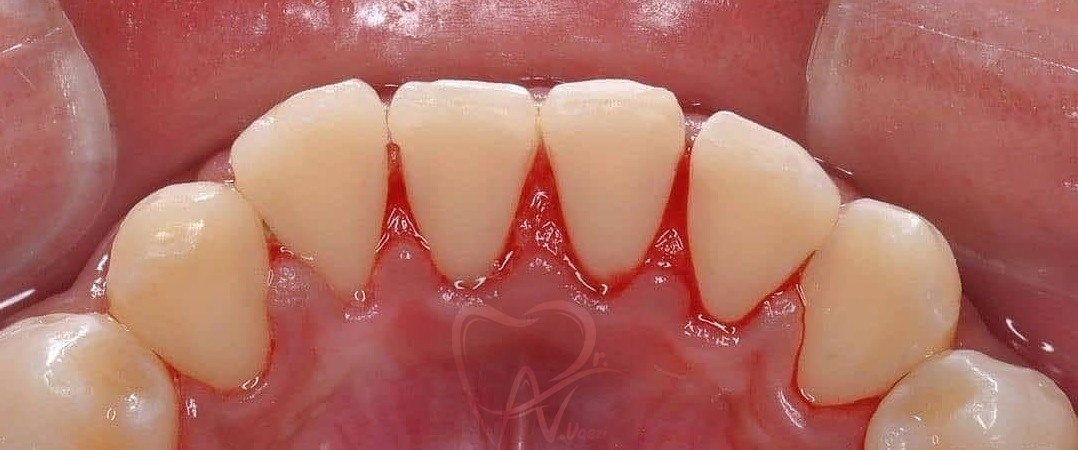

1- حذف جرم های سنگین دندانی با جرم گیری و برساژ

بعد از جرم گیری

قبل از جرم گیری